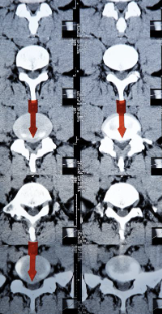

추간판 탈출증 증상 원인 치료방법 추간판 탈출증이란? 알아봐요 추간판 탈출증 증상 원인 치료방법 등 추간판 탈출증에 대해 정리해드리도록 하겠습니다.추간판 탈출증은 디스크가 추간판이라는 구조 안에서 벗어나서 주변 신경을 자극하고 인대를 압박하여 통증을 유발하는 질환입니다. 흔한 증상으로는 허리나 목 부근에서 나타나는 통증, 저림 혹은 근육 경련 등이 있습니다. 원인으로는 나이가 들어서 디스크가 쇠약하여 벗어날 수 있거나, 급격한 강한 충격이나 부드럽지 못한 동작 등으로 인해 디스크가 손상되어 추간판 밖으로 벗어나는 것이 있습니다. 치료는 통증 완화와 함께 특별한 재활 치료 및 수술을 포함할 수 있습니다.

추간판 탈출증은 디스크가 추간판이라는 공간에서 벗어나서 주변 신경을 자극하거나 인대를 압박하여 통증을 유발하는 질환입니다. 이러한 증상은 일반적으로 허리, 목, 어깨 및 다리와 같은 부위에서 나타납니다. 아래는 추간판 탈출증의 일반적인 증상입니다.

추간판 탈출증은 디스크가 추간판이라는 공간에서 벗어나서 주변 신경을 자극하거나 인대를 압박하여 통증을 유발하는 질환입니다. 이러한 증상은 일반적으로 허리, 목, 어깨 및 다리와 같은 부위에서 나타납니다. 추간판 탈출증은 다양한 원인으로 발생할 수 있습니다.